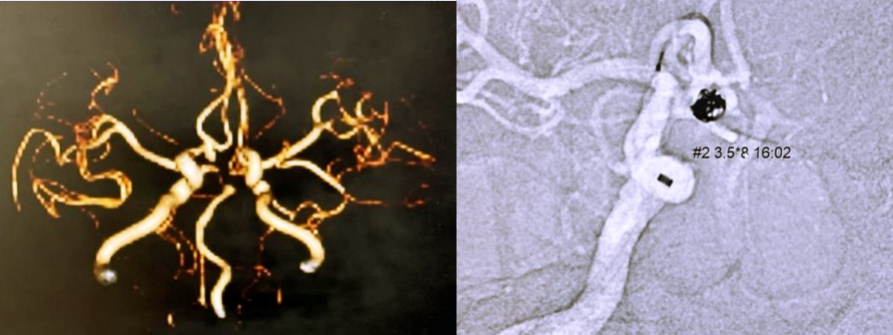

東元綜合醫院神經內科蔡坤璋醫師表示,婦人到院時意識清楚,伴隨頭痛、全身無力。經電腦斷層顯示有瀰漫性蜘蛛網膜下出血,團隊透過血管重組3D圖確定是致死率極高的「隱形炸彈–動脈瘤」釀禍,位置就在左右前大腦動脈與前大腦交通動脈交會處,藏著一顆約5.5×5.5公厘的動脈瘤破裂出血。

醫療團隊立即執行「動脈瘤栓塞術」,手術精細、且難度高,神經內科蔡坤璋醫師利用特殊導管,經由大腿內側股動脈進入,抵達腦血管後,利用柔軟的醫療線圈填滿破裂的動脈瘤,如同用毛線球填塞病灶處,最終手術成功堵住出血點,阻止動脈瘤再次破裂,緊急救回病人生命。婦人在病情穩定後平安出院,並持續回診觀察與復健治療。